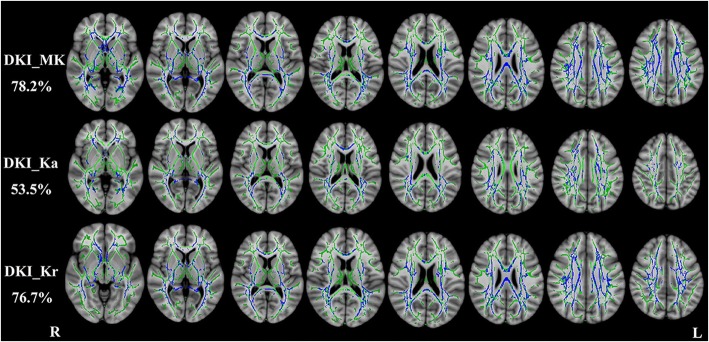

Compared with healthy controls, RRMS patients had significantly decreased DKI-derived kurtosis parameters in WM regions (P < 0.01, two-tailed, FWE corrected) with complex fiber arrangement, such as in the juxtacortical WM and corona radiata. DKI_MK, DKI_Ka and DKI_Kr could detect abnormal diffusion in 78.2%, 53.5% and 76.7% voxels of the whole WM skeleton respectively. Kurtosis parameters are shown in Fig. 1.

Fig. 1.

TBSS shows WM regions with significant differences in the DKI_MK, DKI_Ka and DKI_Kr between RRMS patients and healthy subjects (P < 0.01, FWE corrected). Green represents mean FA skeleton of all participants; blue represents reduction in RRMS patients. The percentage in the left column represents the percentage of the abnormal voxels relative to the whole skeleton voxels for each parameter